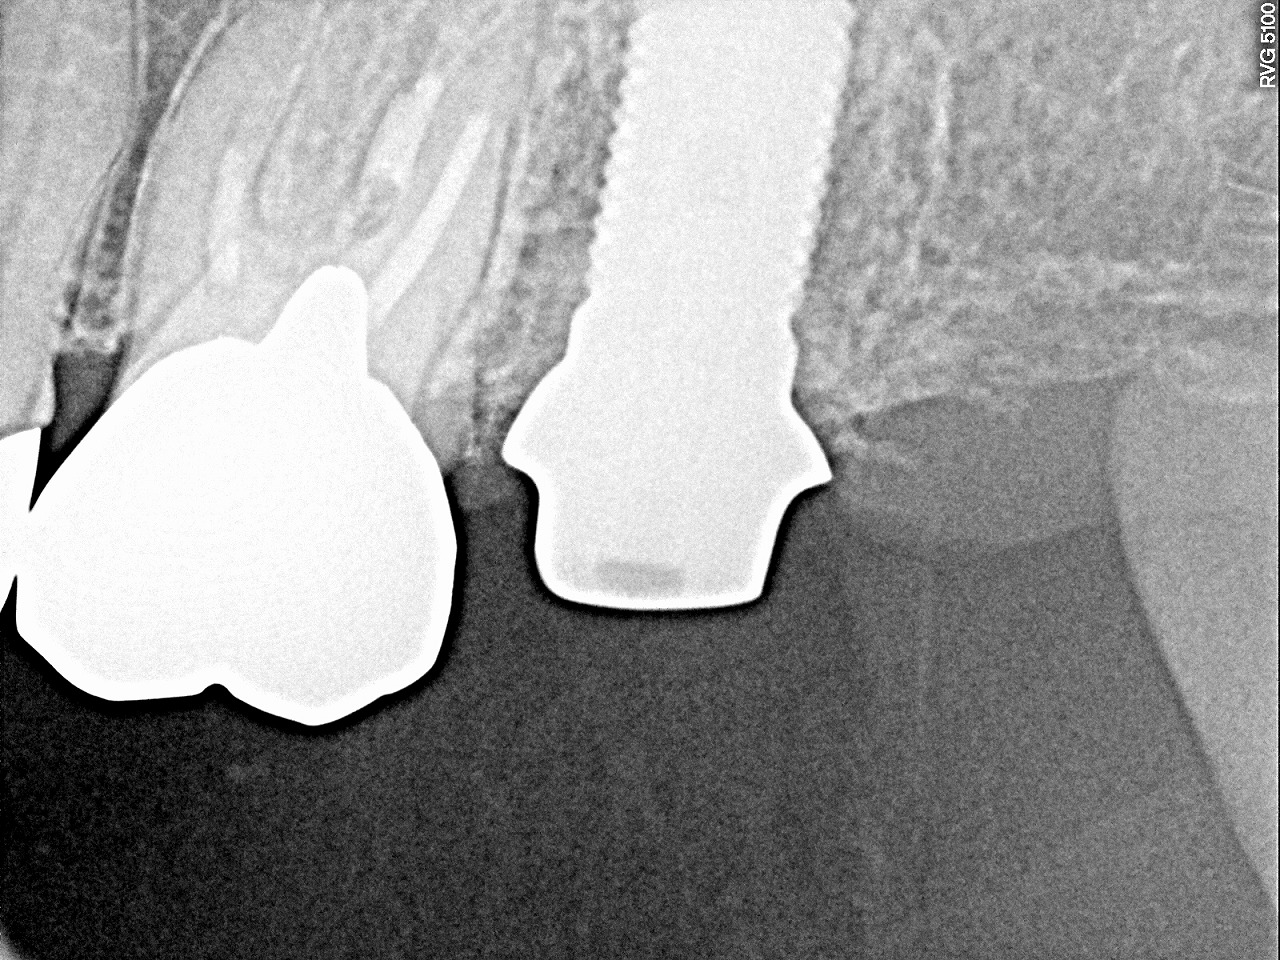

左上7番のインプラント埋入 下のインプラントも歯が割れたため1年前より埋入していました|お知らせ |広島市安佐南区の歯科医院 左上7番のインプラント埋入 下のインプラントも歯が割れたため1年前より埋入していました トップ お知らせ・ブログ お知らせ 左上7番のインプラント埋入 下のインプラントも歯が割れたため1年前より埋入していました 左上7番のインプラント埋入 下のインプラントも歯が割れたため1年前より埋入していました 術前のパノラマになります 術後のパノラマになります 術前のCTになります 抜歯窩がまだくっきりとしています 術後のCTになります カスタムのアバットメントになります アバットメントのデンタルになります オールセラミックになります きれいに仕上がりました Web診療予約 初めての方へ 選ばれ続ける理由 院内設備について 歯が痛いしみる一般歯科 歯がぐらぐらする歯周病 健康な歯を保ちたい予防歯科 子供の虫歯予防をしたい小児歯科 銀歯をセラミックに審美歯科 白い歯を目指しませんか?ホワイトニング 矯正専門医がいるので安心矯正歯科 抜けた歯を補いたいインプラント・入れ歯 医院案内 スタッフ紹介 メリィハウス歯科クリニックオフィシャルホームページ ラベンダー歯科クリニックオフィシャルホームページ お知らせ・ブログ ホーム 診療科目 一般歯科 歯周病治療 予防治療 小児歯科 審美治療 ホワイトニング 矯正歯科 入れ歯・インプラント マウスピース矯正 初めての方へ 院長・スタッフ 設備紹介 医院案内・アクセス メニューを閉じる